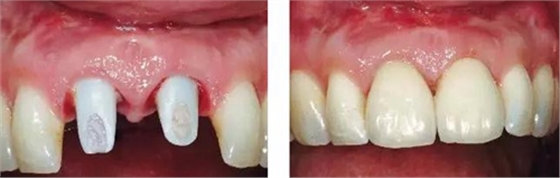

圖11、牙冠戴入1個月以后。軟組織外形良好,形成了良好的弧線形牙齦形態(tài)而沒有瘢痕。保持了原有的色素沉著的顏色和形狀。

圖12、種植術(shù)后1年顯示良好的美學(xué)效果。

圖13、安放全瓷基臺。

圖14、最終修復(fù)體就位,冠頸部較窄。沒有任何牙齦和牙齦乳頭的退縮。

圖15、種植體植入后12個月的微笑相。